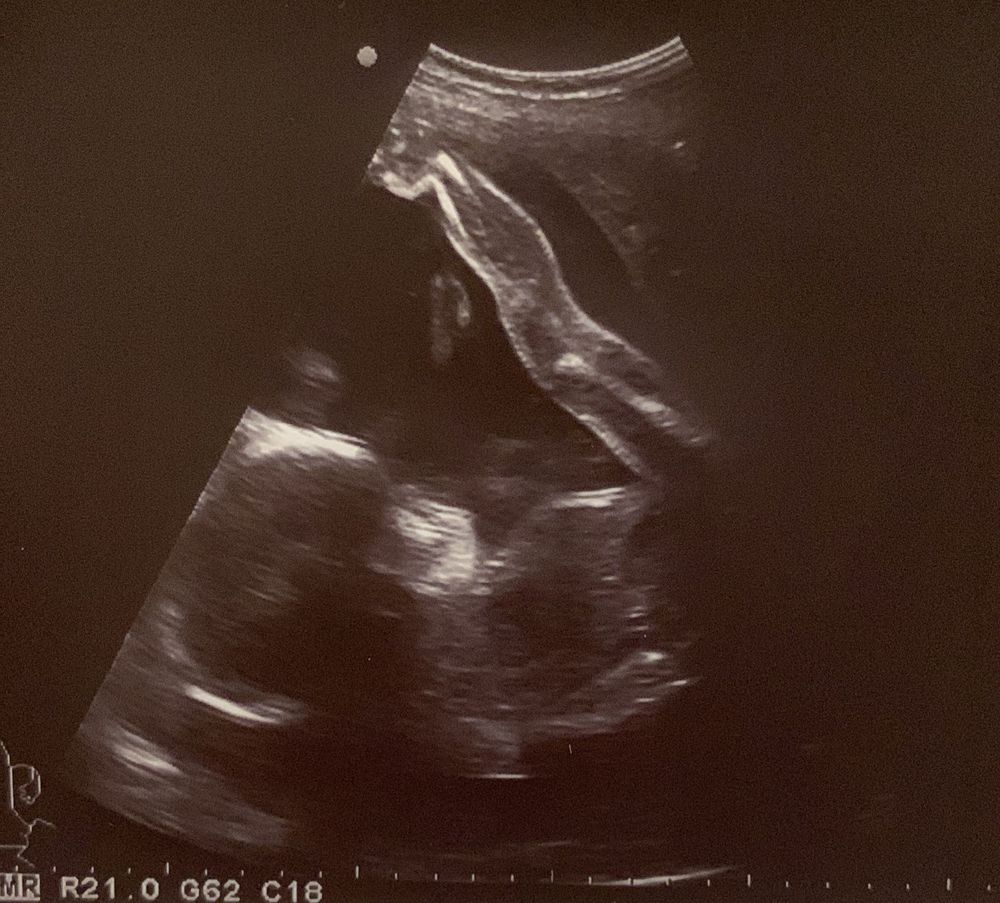

Начну со своего состояния: только похвасталась на той неделе, что все сказочно-прекрасно, как тут же начал болеть и каменеть живот! Вот буквально кликнула "опубликовать" и понеслось.. Благо была запланированная встреча с врачом, где меня успокоили и объяснили суть "проблемы". Дочка у меня, видимо, решила готовиться заранее в олимпийскую сборную. Зачем ждать еще 3-4 года, если можно начать уже сейчас. От таких акробатических этюдов офигела даже врач)) Тк каменный живот у меня расслабляется в течении минуты (плюс минус) и тонуса на УЗИ не было никакого, то дополнительного лечения не назначили. Сказала, что если совсем тяжко будет можно выпить ношпу. Я не любитель УЗИшных фоток, но оставлю это здесь:)))))

Акробатический элемент "березка"

Акробатический элемент "колени в рот при второй вытянутой ноге"

В-общем, получила я не одну типовую фотку с УЗИ, а 4 фотки с представления дочери))